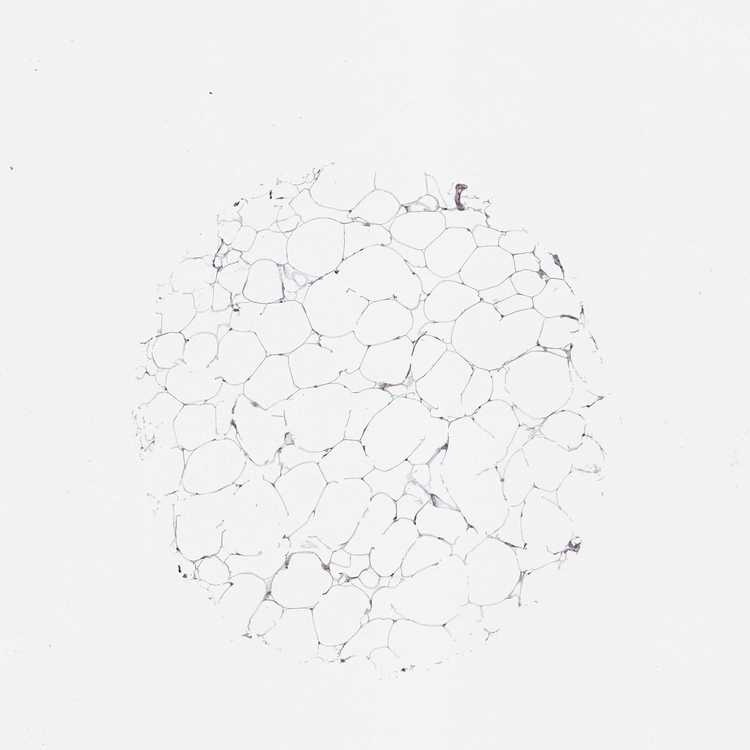

BREAST - Antibody stainingi

Antibody staining in the annotated cell types in the current human tissue is reported as not detected, low, medium, or high, based on conventional immunohistochemistry profiling in selected tissues. This score is based on the combination of the staining intensity and fraction of stained cells.

Each image is clickable and will lead to virtual microscopy that enables deeper exploration of all samples and also displays staining intensity scores, fraction scores and subcellular localization as well as patient and tissue information for each sample.

Antibody HPA049695

Adipocytes Not detected

Glandular cells Medium

Myoepithelial cells Not detected